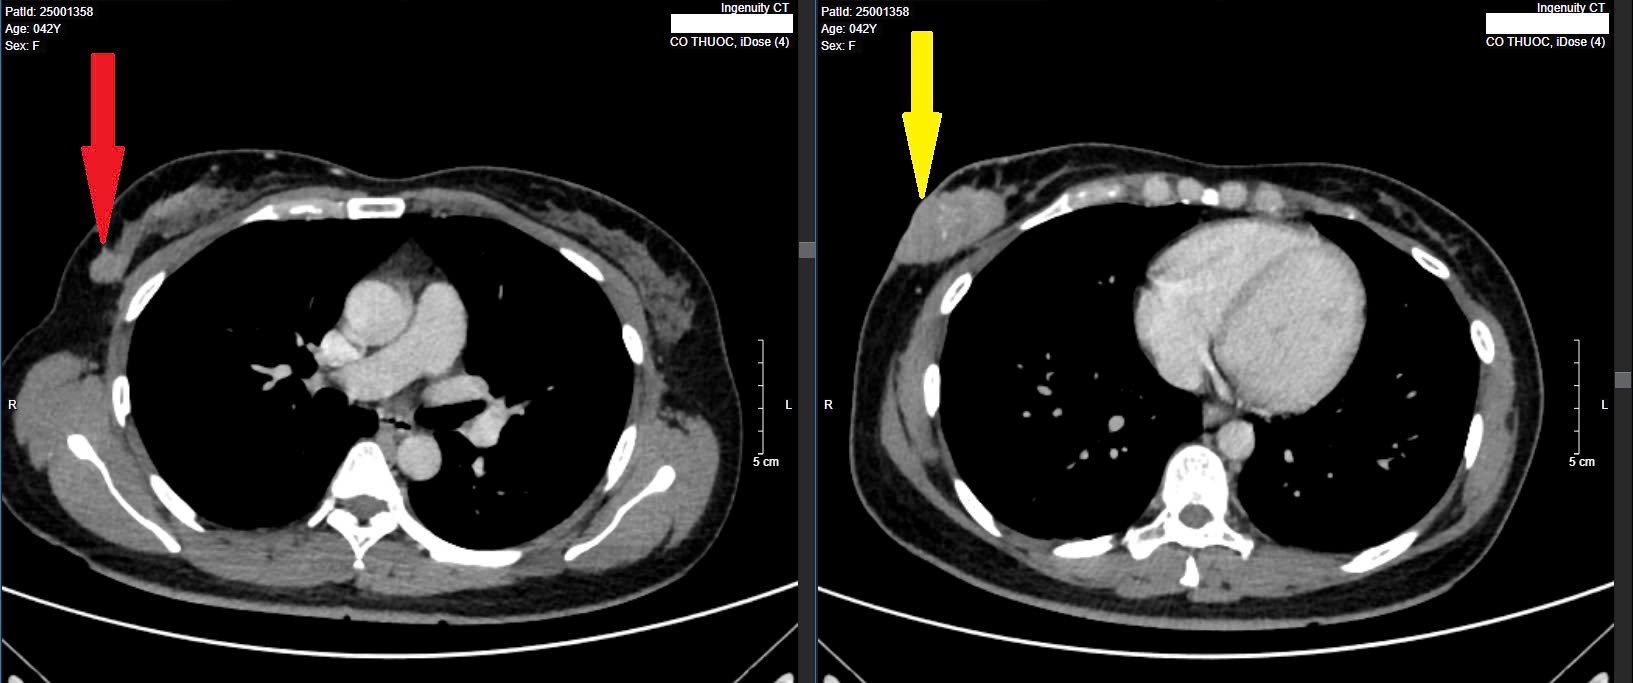

Khối u nguyên phát ban đầu (mũi tên vàng) và u vệ tinh mới xuất hiện (mũi tên đỏ). Ảnh: BSCC

Trực tiếp thăm khám cho bệnh nhân, Thạc sĩ, bác sĩ Nguyễn Duy Anh, Trung tâm Ung bướu, Xạ trị và Y học hạt nhân Quốc Tế tại một bệnh viện ở Hà Nội cho biết, sau khi khám lâm sàng và chỉ định chụp CT-scan toàn thân cho bệnh nhân phát hiện có khối u vú phải kích thước 25x52mm, nhiều hạch to tròn, phổi hai bên có các nốt mờ màng phổi.

Với trường hợp trên, tình trạng bệnh nhân được xác định đã di căn phổi ở giai đoạn 4, lúc này sẽ không thể chữa khỏi được căn bệnh với y học hiện tại. Người bệnh sẽ phải liên tục điều trị để kìm hãm căn bệnh, dẫn tới suy sụp tâm lý và còn tăng chi phí khám chữa bệnh cùng chi phí liên quan khác. Nguy cơ bệnh kháng thuốc sẽ tăng cao dần theo thời gian, nhất là càng về thời gian cuối. Ngoài ra, đánh giá tới khối u nguyên phát tại vú phải hiện có xâm lấn phần mềm xung quanh sẽ có thể gây đau, loét da tuyến vú (gây chảy máu-dịch) ảnh hưởng tới thẩm mỹ.